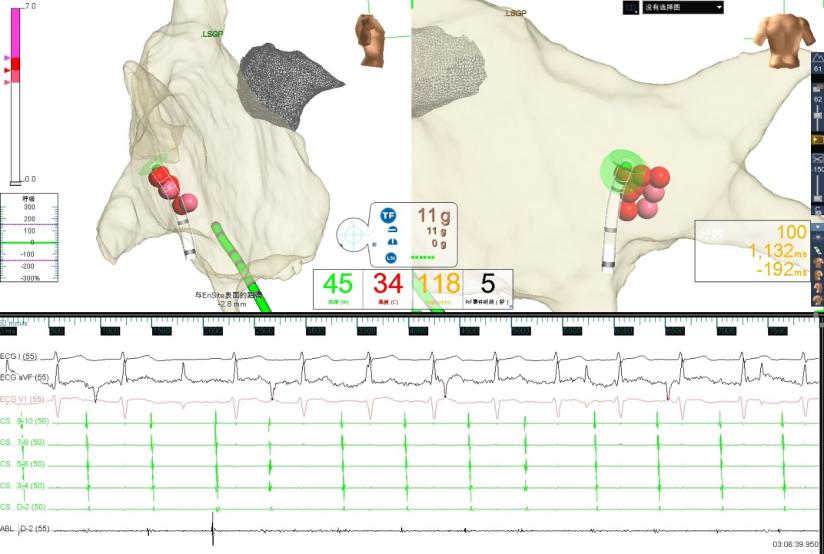

图2 消融右前GP时窦性心房频率增快,房室非1:1下传,心室率稍增快

图3 消融右下GP时房室传导恢复为1:1下传且心室率明显增快

经与患方充分沟通治疗方案后,5月9日,在寿锡凌教授指导下,酉鹏华副主任医师、韩稳琦博士、赵永勇主治医师等为患者局麻下成功行经导管心脏迷走神经节消融改良术。术中先行心脏腔内电生理检查术,消融前测窦房结恢复时间(SNRT):1404ms,房室结文氏点(CSNRT):700ms,依次消融左房左上神经节丛(LSGP)、左房左下神经节丛(LIGP)、左肺静脉间神经节丛(MTGP)、左房右前神经节丛(RAGP)、左房右下神经节丛(RIGP),消融RAGP时窦性心房频率从40-46次/分提升至95-100次/分,但表现为房室传导阻滞,房室非1:1传导特点,心室率提升不明显,消融RIGP时房室结迷走张力减低,房室传导明显改善,房室呈1:1传导,心室频率提升至95-100次/分。

术后患者未再出现头晕症状,复查24小时动态心电图,患者平均心室率由术前45次/分提升至术后77次/分,最慢心室率由术前31次/分提升至术后60次/分,最快心室率118次/分。复查直立倾斜试验为阴性,未再出现心脏停搏,且无围术期相关并发症,患者非常满意,术后第二天出院。